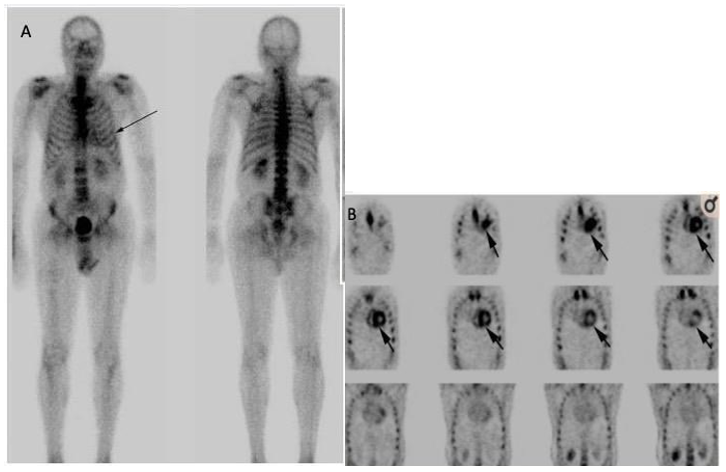

We present a case report from our Nuclear Medicine department at Guy's and St Thomas' NHS Foundation Trust. A patient presented with a known history of malignant neoplasm of the prostate, type 2 diabetes, hyperlipidemia NOS, chronic kidney disease, and no history of cardiac myopathies. The patient was scheduled for an HMDP bone scan as a prostate cancer patient complaining of hip bone pain. The scan was carried out as normal bone scintigraphy with three hours post-injection delayed phase of whole-body imaging. While reviewing and reporting the whole-body images, a note was made of the clear, intense uptake in the heart visually assed of a Perugini grade 2. The findings were highly associated with amyloidosis (Figure 11). A recommendation for a referral to the cardiology was made for further investigation. However, no further investigation was done at six-week intervals by the time of publication.

Figure 11 Demonstrating HMDP bone scan of a patient undergoing cardiac amyloid study showing Perugini Grade 2 cardiac uptake. Kindly contributed by Dr Dhruba Dasgupta, Guy's and St Thomas' Hospital.

The following published case of ATTR CA diagnosed due to incidental myocardial uptake during bone scintigraphy is similar to our case from Guy's and St Thomas' NHS.

Foundation Trust. In this case, an 83-year-old man underwent prostatectomy for prostate cancer with a known history of carpal tunnel syndrome. The patient underwent serial (99mTc-HMDP) scintigraphy to evaluate bone metastasis due to prostate cancer. Incidental finding of cardiac uptake (visual grade, 2; heart-to-contralateral (H/CL) ratio, 1.70) was observed. However, no further investigation was made on suspected ATTR since the patient had no symptoms of heart failure. 99mTc-HMDP Bone scan was repeated Six years later for re-elevation of prostate-specific antigen level. The cardiac uptake was found to be greater (visual grade 3, and H/CL ratio: 2.32), echocardiography showed the left ventricular thickness, and endomyocardial biopsy showed amyloid deposition in the cardiac. The presence of ATTR was confirmed by immunohistochemistry.51